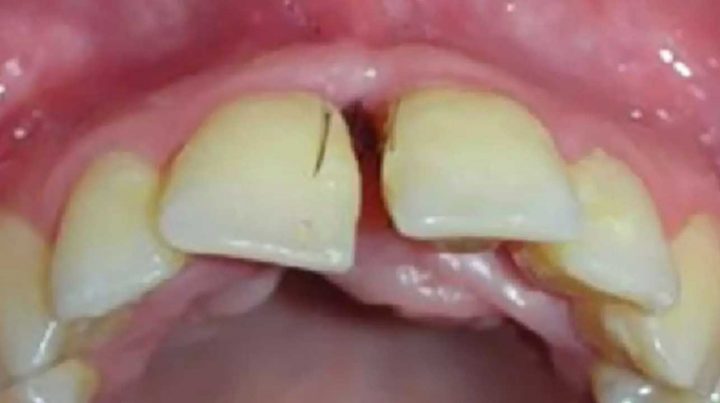

Le journal médical Oral Surgery, Oral Medicine, Oral Pathology and Oral Radiology rapporte un cas extrême d’hirsutisme assez particulier. Une jeune femme de 25 ans, atteinte du syndrome des ovaires polykystiques a remarqué la pousse de poils entre les dents. L’une des conséquences de ce syndrome, qui entraine un dérèglement hormonal est la pousse inhabituelle des poils. Mais un tel cas de poils aux dents est vraiment rare. « En examinant son visage on peut remarquer la présence d’une pilosité inhabituelle au menton et dans la zone du cou », peut-on lire dans l’article médical. « Un examen buccal révèle la présence de poils bruns, semblables à des cils ». Des photos de l’examen accompagnent l’article.

Des poils, tels des cils, ont poussé dans ses gencives

Les poils « ont été enlevés et les tissus ont été analysés. Un an plus tard, la patiente est revenue avec la présence encore plus importante de poils autour des gencives et dans les sillons gingivaux. » Ce genre de pathologie serait extrêmement rare. La cause de la présence de poils dans cette zone du corps est encore inconnue. « Une étude de cas précédents révèle cinq autres cas, mais la plupart indiquaient seulement la présence d’un seul poil à différents endroits de la cavité buccale ».